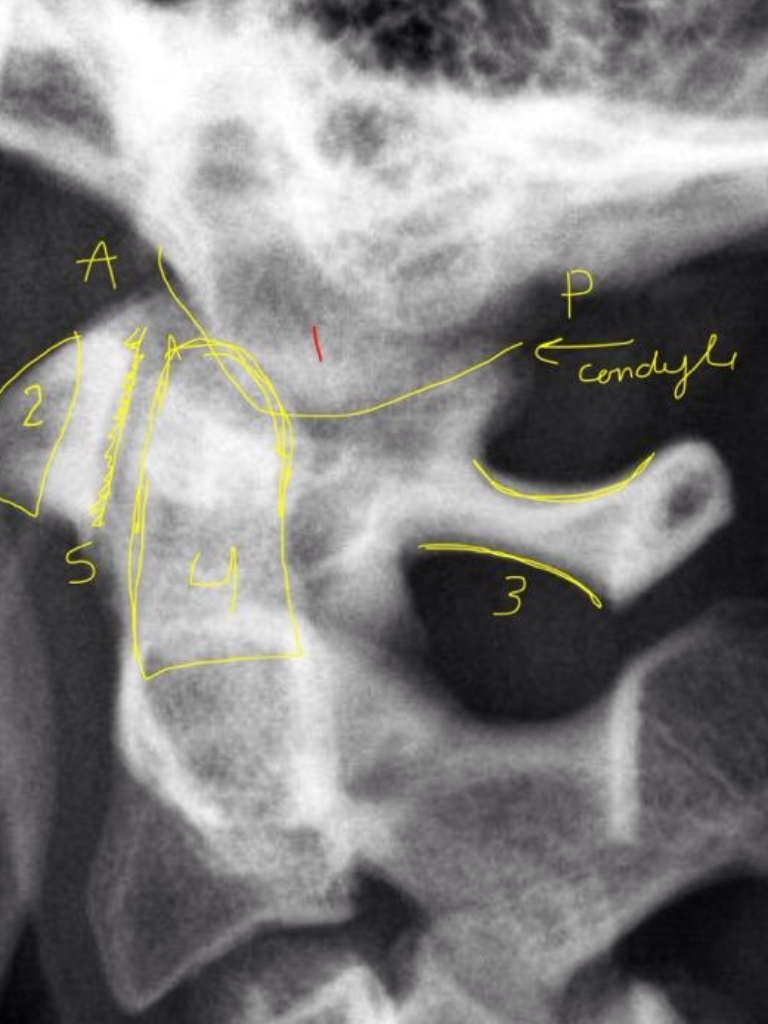

4

A

S2 tubercle

5

Pubic symphysis

6

Sacral Grooves

3

Inferior aspect of ischial tuberosities

2

Superior aspects of iliac crest